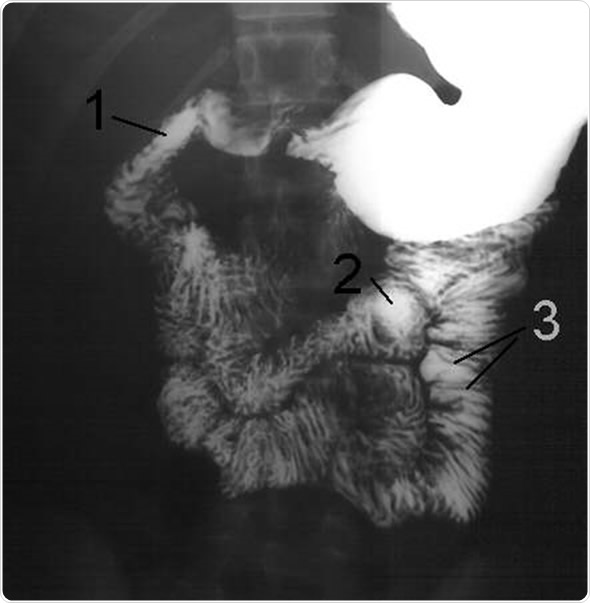

A barium meal is a diagnostic test used to detect abnormalities of the esophagus, stomach and small bowel using X-ray imaging. X-rays can only highlight bone and other radio-opaque tissues and would not usually enable visualization of soft tissue. However, infusion of the contrast medium barium sulfate, a radioopaque salt, coats the lining of the digestive tract, allowing accurate X-ray imaging of this part of the abdomen.

The images produced are fluoroscopic and can be viewed in real-time as well as on plates.

Some initial images are taken to check that the barium has passed through the esophagus, and into the stomach and small bowel. The radiographer then takes a series of X-ray images over time as the barium contrast moves through the digestive system. This may mean images are taken over anywhere between 1 and 4 hours. Once the barium contrast has passed through to the large bowel or the colon, more pictures are taken. The whole test may take around 5 hours.